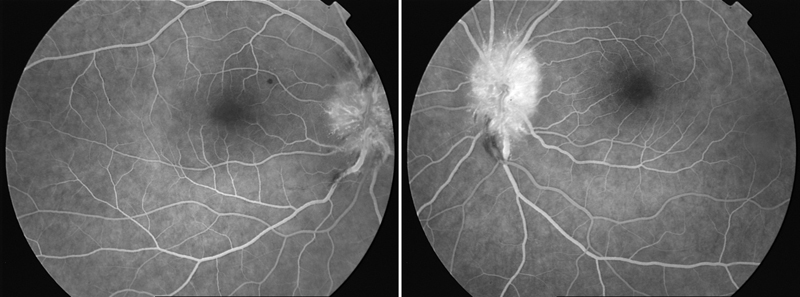

Figura 2). Se realiza angiografía fluoresceínica (AFG), evidenciándose imágenes compatibles con papilitis bilateral (

Figura 3).

Figura 3. Angiografía por fluoresceína: hiperfluorescencia precoz a nivel papilar bilateral sugestivo de neurorretinitis bilateral.